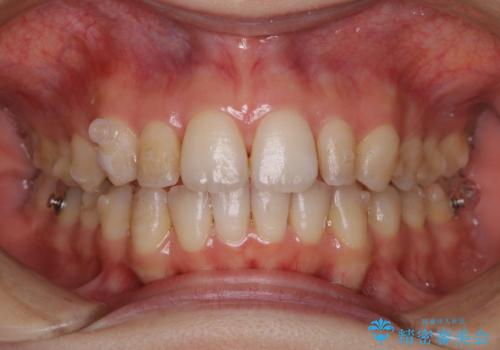

1日で着色を除去し綺麗な歯に

- 前歯の汚れが気になるため、綺麗にしたいとのことで来院されました。PMTC30分コースを行いました。

毎日丁寧に歯磨きをしていても、日常生活での飲食物などにより着色してしまうことはあります。PMTCでは、歯の表面の凸凹にミネラルを補給して、ツルツルの表面に仕上げます。定期的にPMTCを行うことにより、歯質の強化になり着色がつきにくい状態になります。

また、歯と歯の間に歯石がたまるとフロス・糸ようじなどが通らなくなってしまいます。定期的に機械的なクリーニングを行い健康的な歯肉の状態を保つことが大切です。